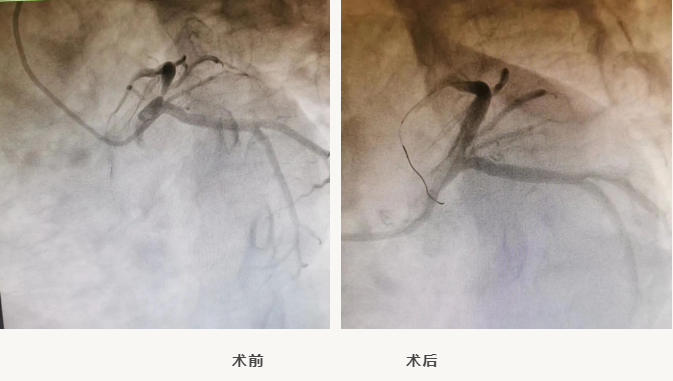

近日,星城院区心血管内科导管室顺利完成2例IVUS(血管内超声)指导下精准支架植入术。

张先生在2022年初做冠脉CTA检查时,发现前降支重度狭窄,一直未行冠脉造影检查,后来听说星城院区导管室已正式启用,遂来星城心血管内科就诊,行冠脉造影检查发现前降支开口狭窄约95%,因为此处病变相当于大树根部的分叉处,一旦处理不当,患者可能会有生命危险。

星城院区心血管内科王志勇副主任医师联合北京阜外医院介入专家及介入团队其他成员,全面评估患者病情后,决定在IVUS的指导下,精准植入支架——

球囊扩张、IVUS检查、支架植入、复查IVUS,整个手术不到一小时,复查IVUS和造影结果非常满意,患者无任何不适。